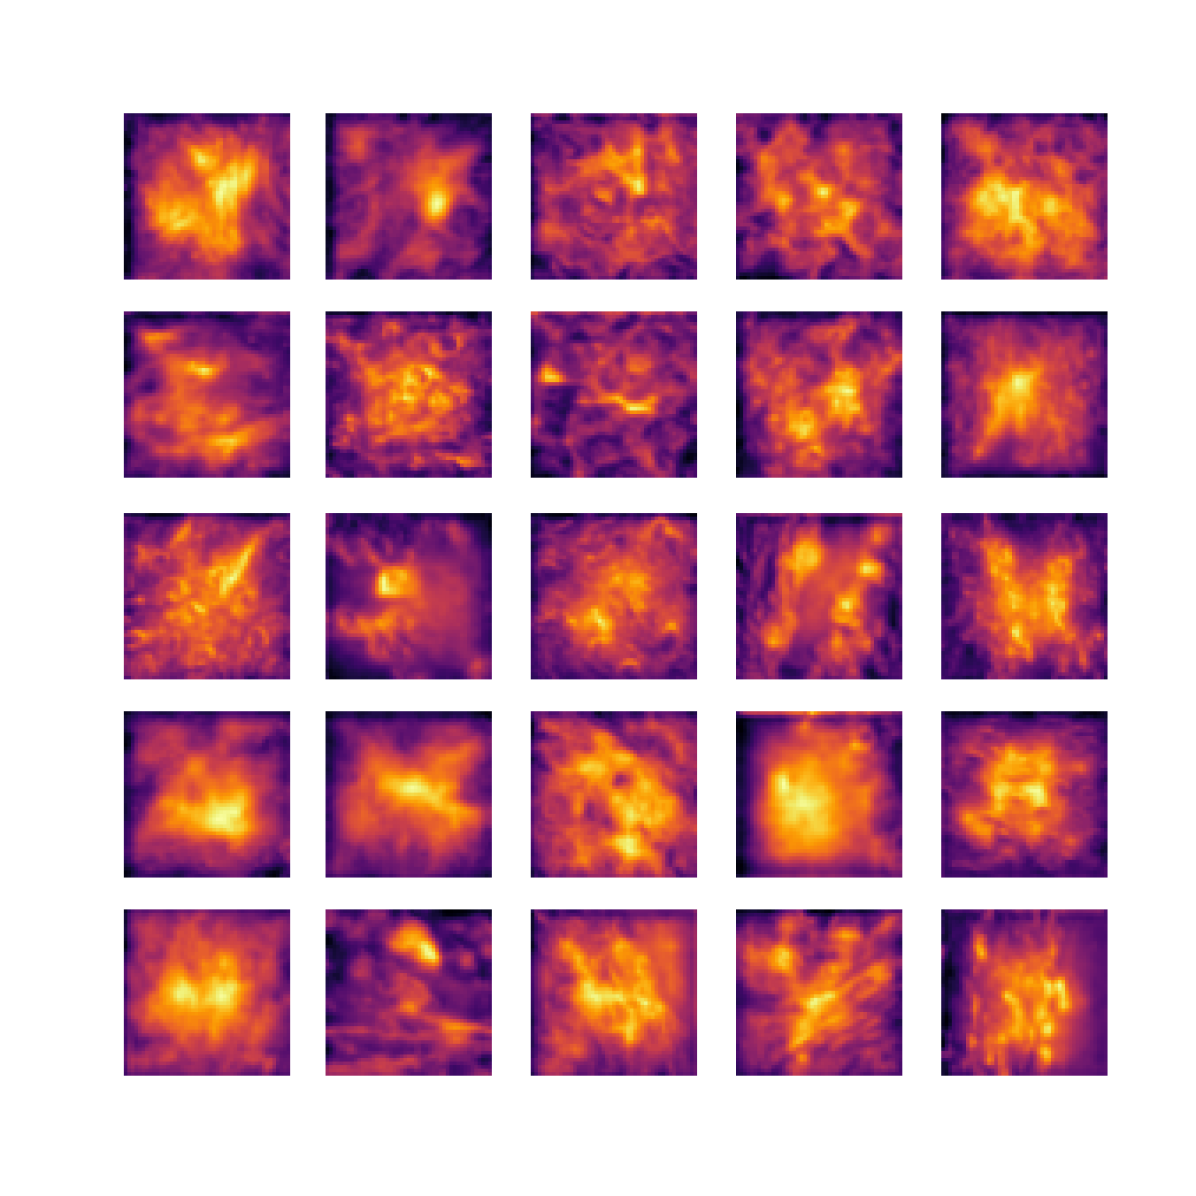

We also analyse the activation maps for each model using GradCAM as described in section S3. This offers more insight into the areas of the image which are contributing most heavily to the models’ representations. In Figure 4(b) we present some representative examples, however, a larger selection which was chosen at random is presented in Figures S10 to S25. The larger selection makes it easier to see the emergent patterns, including that privileged Siamese models tend to mainly identify features which are strongly present in both inputs, while unprivileged Siamese models tend to learn more diffuse features that are not specific to one cell phenotype or image region. TriDeNT ♆ incorporates both sets of features, learning both features specific to the privileged data and more the general features associated with unprivileged Siamese networks.

We can see in Figure 4(b) panel A that for ERG, the privileged Siamese model focuses almost exclusively on any nuclei which could be endothelial cells. As there are very few endothelial cells in the dataset, it could be an effective strategy to identify anything that could potentially be an endothelial cell to minimise the difference between the representations of the H&E model and the IF mask model. In the corresponding unprivileged Siamese image, we see that the model identifies some of these nuclei, albeit less strongly, but also focuses heavily on the other tissue and even the background, while strongly fixating on two spots of debris in the center of the image. This model has less ‘incentive’ to learn the weak features related to endothelial cells as these occur rarely and are not easy to detect, while more generic strong features such as the presence of connective tissue and the prevalence of background are more common and predictable from augmented images. We see that TriDeNT ♆ combines these two feature sets, strongly identifying nuclei while also identifying the connective tissue.

In panel C we see a similar pattern, with the privileged Siamese model fixating solely on the nuclei, while the TriDeNT ♆ model takes a more balanced approach. The unprivileged Siamese model appears to focus on a single cluster of nuclei while neglecting others, and similarly identifies an area of fibroblasts with its distinctive pattern but does not others.

In contrast to panels A and C which represent models with poor privileged Siamese results, panels B and D represent models whose privileged Siamese results were comparable to both TriDeNT ♆ and even the supervised baseline. It is therefore interesting to note that there are far more similarities between the privileged Siamese and TriDeNT ♆ models in both cases. Particularly in panel B, TriDeNT ♆ and the privileged Siamese model return virtually identical heatmaps, with both strongly identifying epithelial nuclei and neglecting the same areas of connective tissue. The unprivileged model in this case appears to focus solely on the centre of the image, giving a significantly different heatmap to the other panels.

Panel D again shows the previous pattern, with the privileged Siamese model identifying the features strongly present in the privileged data – fibroblasts – while neglecting the nuclei present. TriDeNT ♆ also strongly identifies the connective tissue, but, unlike the privileged Siamese model, does not completely neglect the nuclei. The unprivileged Siamese model primarily identifies background, and does not appear to identify the nuclei in this example.